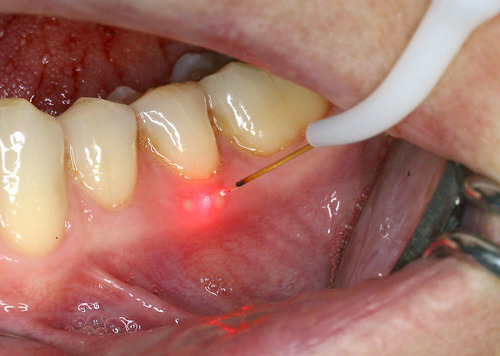

Par exemple, sur des aphtes douloureux (fig. 20) un rayonnement laser est rapproché progressivement jusqu’à une disparition quasi complète des sensibilités (fig. 21).

Fig. 21 Traitement avec un rayonnement laser pénétrant